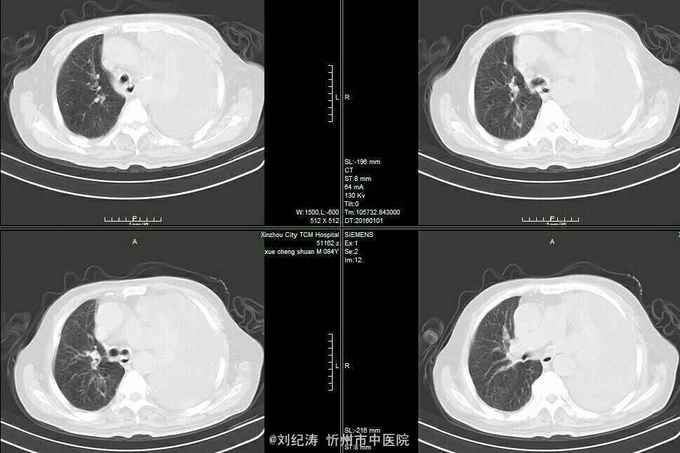

12.21 ,今天复查ct:胸腔积液明显减少,左侧稍增多一点

左肺癌并左侧大量胸腔积液,左肺不张

胸腔积液ct图片

胸腔积液ct表现图片